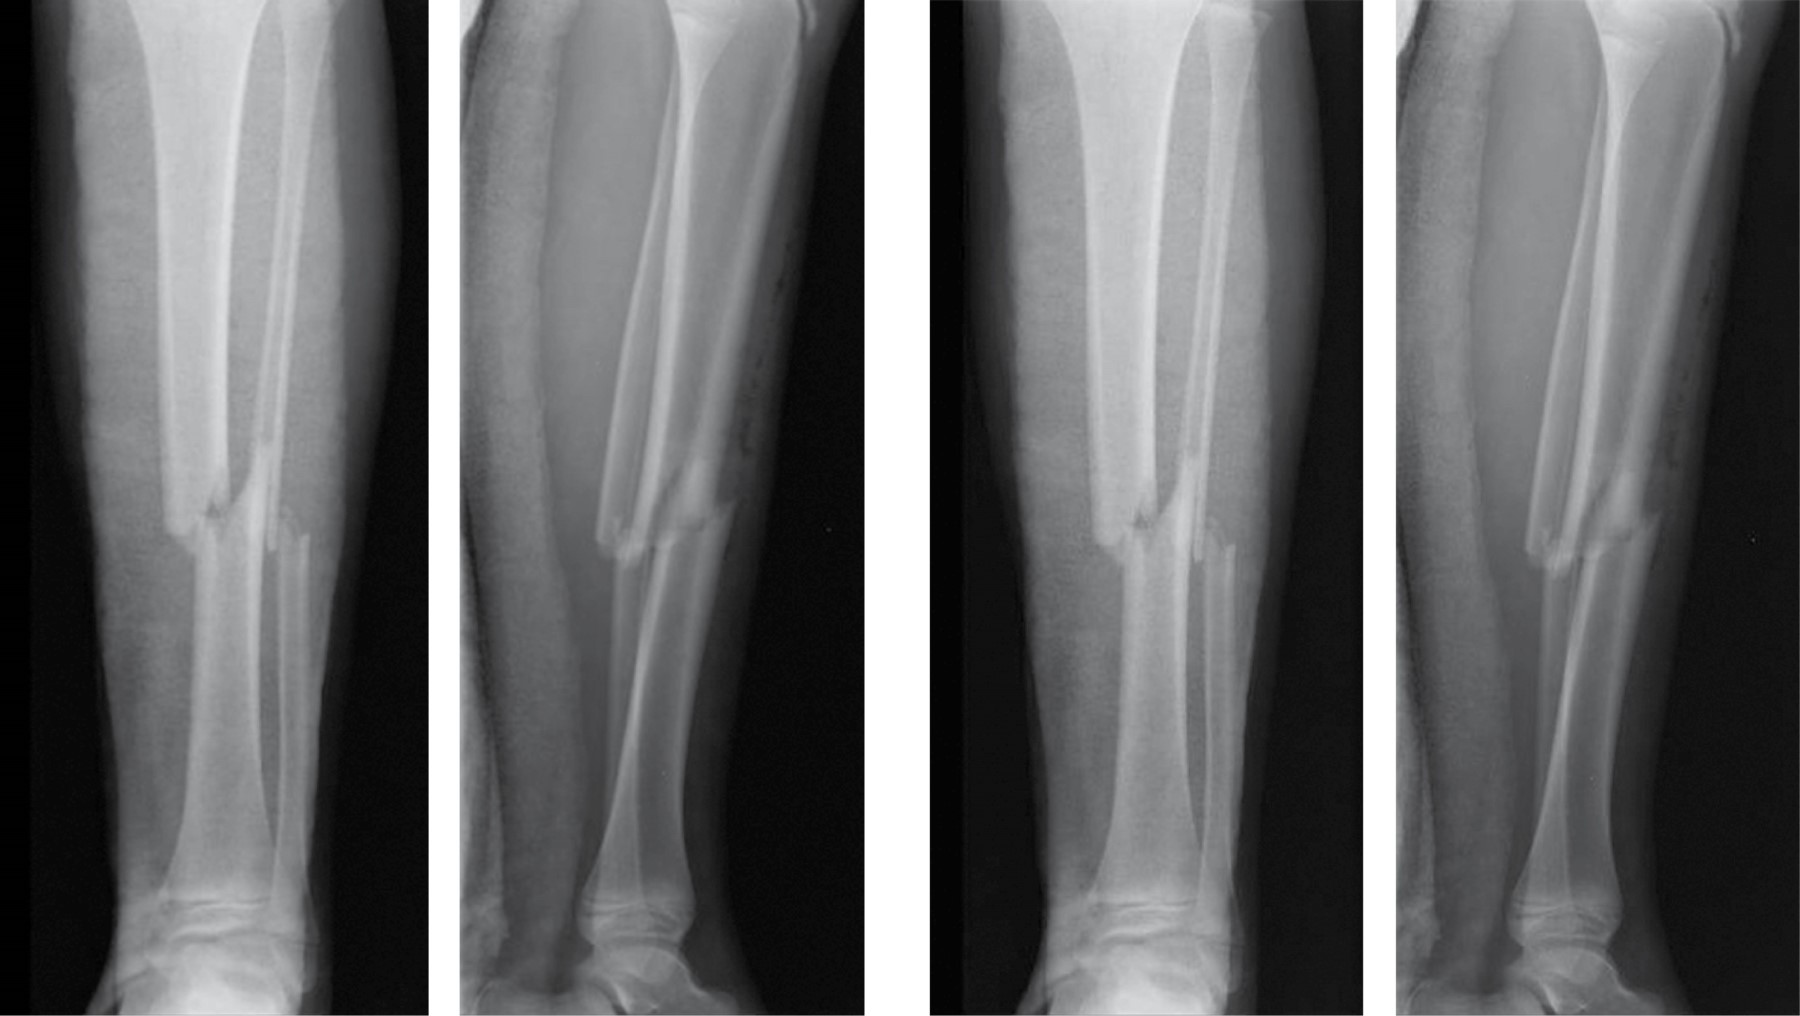

Se realizó un estudio retrospectivo, analítico y descriptivo de pacientes con pérdida ósea de miembros inferiores con pseudoartrosis infectada, que fueron tratados mediante transportación ósea con la técnica de De Bastiani (Tabla 1), con el sistema de fijador externo tipo monorriel. Se incluyeron en el estudio aquellos pacientes con pseudoartrosis infectada, de uno u otro sexo, con una pérdida ósea de tibia de más de 5 cm, manejados en el servicio del Centenario Hospital "Miguel Hidalgo" (Figura 1). Se excluyeron los pacientes que no presentaron infección de pseudoartrosis. Se realizó una planeación quirúrgica para todos los casos mediante un protocolo preoperatorio general que incluyó estudios de laboratorio preoperatorios completos con reactantes de fase aguda, y se solicitaron controles de radiografías en la consulta externa. Sólo una paciente no comenzó el tratamiento inicial en este hospital, por lo que no contamos con las radiografías iniciales (Figura 2). Los resultados después de la corticalización del segmento transportado fueron evaluados desde el punto de vista óseo y funcional, utilizando el sistema descrito por Paley y colaboradores. Para los resultados óseos se valoraron cuatro criterios: consolidación, infección, deformidad y discrepancia de extremidades.9 Los resultados funcionales se basaron en cinco criterios: cojera significativa, deformidad rígida en equino del tobillo, distrofia de tejidos blandos (manifestada por hipersensibilidad dérmica o insensibilidad), dolor e inactividad (que el paciente quedara inhabilitado para las actividades diarias). De acuerdo con este sistema, un excelente resultado funcional es el que logra actividad sin ninguno de los otros criterios; un resultado bueno es el que realiza actividad pero con uno o dos de los otros cuatro criterios; regular es cuando logra actividad pero presenta tres o cuatro de los otros criterios o ameritó amputación; y malo en aquel que no logra actividad individual a pesar de los otros criterios.5

El método de De Bastiani consiste en la estabilización de los fragmentos comprometidos con tornillos troncocónicos no transfictivos, los cuales se fijan a un riel rígido con tres cabezales deslizantes (sistema de fijación externa tipo monorriel).2 Con el paciente en decúbito dorsal bajo bloqueo subaracnoideo en mesa radiolúcida y con intensificador de imágenes, se determinan líneas paralelas a la superficie articular, se colocan tres cabezales provisionales en regleta de elongador, se coloca un primer tornillo en cabezal proximal paralelo a articulación de rodilla, el segundo tornillo en cabezal distal paralelo a articulación de tobillo y un tercer tornillo en cabezal intermedio paralelo a la diáfisis de la tibia, después se colocan los tornillos restantes, quedando tres tornillos por cabezal, se cambian cabezales provisionales por los definitivos (Figura 3). Después se realiza incisión de 1 a 1.5 cm en la región proximal o distal según el sitio seleccionado para la corticotomía hasta periostio, se incide éste de manera longitudinal y se procede a perforar agujeros en las caras anteromedial y anterolateral del hueso para perforar la cortical posterior con broca 3.2 mm, mismos que se realizan con la menor distancia entre sí. A continuación, los agujeros se unen con un osteótomo una vez completada la osteotomía, porque la parte posterior se rompe de manera espontánea debido a la tensión aplicada antes del montaje. Se separan los segmentos mediante el distractor para asegurar que la osteotomía es completa y se confirma con el intensificador de imágenes. Se vuelven a aproximar los segmentos a distraer, sometiéndolos a una compresión leve y se aprietan las tuercas de bloqueo. Se cierra el periostio y la herida sin dejar drenajes. Se entrena al paciente y familiares sobre cómo realizar la distracción, cuándo iniciarla, frecuencia y sentido de la vuelta de la unidad de compresión-distracción, se le recomienda al paciente anotar en un cuaderno hora y fecha de distracción y sus observaciones como sensación de tracción, dolor o cualquier eventualidad. De no existir contraindicación alguna, se egresa al segundo día del postoperatorio. La fase de reposo dura en promedio 10 días. La distracción se realiza a razón de 1 mm por día, girando cuatro veces al día un cuarto de vuelta en sentido antihorario la unidad de compresión-distracción (0.25 mm cada 6 horas). Este promedio de distracción se acelera temporalmente cuando se observa una osificación rápida, o se reduce si la osificación es lenta o el paciente padece dolor o contractura muscular. La distracción es vigilada mediante controles radiográficos. Se cita a los 10 días del postoperatorio para valorar las heridas, retirar los puntos y verificar que entendió cómo iniciar la distracción. Tres citas semanales al inicio y quincenales posteriormente con radiografías de control. La fase de reposo dura en promedio un día. La distracción se realiza a razón de 1 mm por día, girando cuatro veces al día un cuarto de vuelta en sentido antihorario la unidad de compresión-distracción (0.25 mm cada 6 horas). Este promedio de distracción se acelera temporalmente cuando se observa una osificación rápida, o se reduce si la osificación es lenta o el paciente padece dolor o contractura muscular. La distracción es vigilada mediante controles radiográficos. Se cita a los 10 días del postoperatorio para valorar las heridas, retirar los puntos y verificar que entendió cómo iniciar la distracción. Nueva cita a los 10 días con radiografía de control para valorar que la distracción se realiza de manera correcta. Se le recomienda la carga parcial de aproximadamente 15 kg. Después se cita cada 30-40 días con radiografías de control para comprobar que se produzca la osteogénesis, en cuyo caso se continúa la transportación. Si la densidad del neoformado es pobre pero uniforme, se suspende la distracción por una o dos semanas. Si el neoformado es irregular, se comprime el segmento uno o dos centímetros a la misma velocidad de la distracción hasta que el callo sea uniforme, a continuación se reinicia la transportación. Al final de la transportación, cuando hay contacto de los dos fragmentos, la radiografía debe mostrar un callo uniforme (Figura 4). Se bloquea el cabezal del alargador para mantener el hueso nuevo en neutralización estable, el compresor-distractor es entonces retirado. Cuando así se requiere, una nueva cirugía puede realizarse para reavivar los bordes de la zona de contacto y colocar injerto para acortar el tiempo de consolidación, el soporte de carga en esta fase de neutralización se incrementa gradualmente en función del grado de mineralización del neoformado. Cuando la radiografía demuestra que el segmento es uniformemente denso y opaco, se dinamiza el elongador aflojando la tuerca del cabezal proximal y se bloquean las del cabezal medio y distal. Una vez que se ha logrado la corticalización completa, se procede al retiro del elongador y los tornillos troncocónicos, se realiza en quirófano y bajo anestesia general endovenosa (Figura 5).

De acuerdo con los criterios de selección, fueron incluidos un total de dos pacientes con pérdida ósea de tibia y fémur por pseudoartrosis infectada que recibieron tratamiento mediante transportación ósea con la técnica de De Bastiani durante el periodo de estudio. Uno fue del sexo masculino (50%) y uno femenino (50%). La edad promedio fue de 16 años (rango de 15 a 17 años). Una de las pérdidas óseas (50%) se presentaron como secuelas de fracturas expuestas y una de fracturas cerradas (50%). La fractura expuesta fue en la tibia izquierda y la cerrada en la tibia izquierda. Una de las fracturas se reportó por causa espontánea, idiopática, la fractura expuesta por caída de una caja de camioneta. En la fractura expuesta, el tratamiento inicial consistió en desbridamiento y fijación externa, con reducción abierta, fijación interna con placa de compresión bloqueable (LCP) 3.5. Para la fractura cerrada de tibia en reducción abierta fijación interna con placa LCP 3.5. Sólo un paciente no comenzó su tratamiento quirúrgico en este hospital (fractura cerrada de tibia) llegado a la consulta externa con placa fatigada y en pseudoartrosis infectada. La longitud de pérdida ósea promedio fue de 10 cm (rango de 7 a 11 cm). El sitio de la corticotomía en los dos casos fue diafisario proximal. La transportación ósea se inició en promedio con los 15 días después de la corticotomía (rango de 10 a 15 días). A los dos pacientes se les realizó técnica Masquelet durante el procedimiento. La velocidad de distracción promedio fue de 0.85 mm/día (rango de 0.57 a 0.98 mm/día). El tiempo de consolidación y corticalización del segmento transportado fue de 14.5 meses (rango de 6 a 22 meses), sólo en un caso fue de tres años (el caso de la fractura expuesta). El índice de corticalización promedio fue de 1.9 cm/mes (rango de 0.8 a 3.2 cm/mes). Los pacientes lograron la consolidación del segmento transportado aunque uno de los casos aún continúa con el fijador monorriel. Dos pacientes presentaron deformidad residual del segmento transportado, uno con retroverso de 6o y valgo de 5o; el segundo presentó anteverso de 15o. Discrepancia de las extremidades inferiores ocurrió en los dos pacientes, de 1.5, 2 cm y 2 cm. De acuerdo con el sistema de clasificación de Paley, dos pacientes tuvieron resultados óseos excelentes (71%) y uno buenos (29%) (Tabla 2).

Figura 2